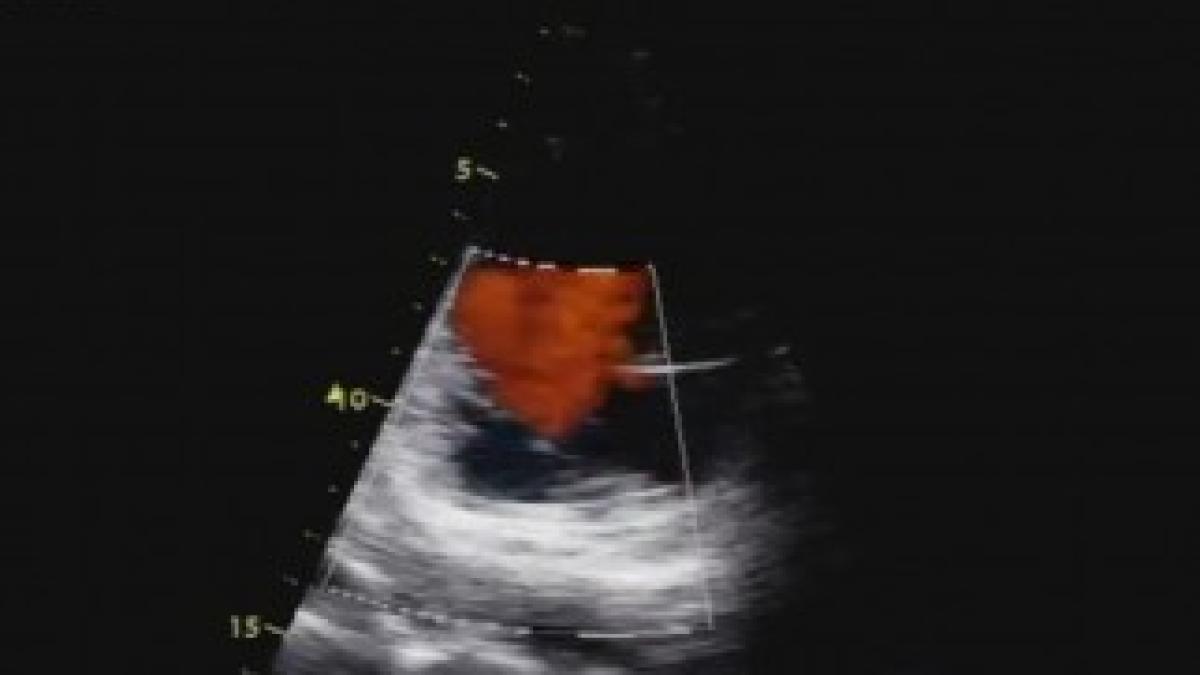

În imaginea ecografică se văd două zone întunecate separate de o fâșie albă (partea din interiorul dreptunghiului roșu). În mod normal, valva care face trecerea din atrii în ventriculi trebuie să fie suplă, elastică şi să se închidă perfect.

Clipul  arată o vegetaţie imensă, produsă de stafilococul injectat odată cu drogul, pe valva ce face trecerea între camerele inimii. În mod normal, imaginea Doppler arată fluxul de sânge care în timpul contracţiei ventricolului ar trebui să meargă în artera aortă, iar valva să se închidă complet.

La testul Doppler color, din al doilea clip, imaginea albastră indică un flux normal, iar culoarea către orange arată turbulenţa de flux, respectiv un aspect anormal. Din cauza vegetaţiei de pe valvă, aceasta nu se închide şi fluxul de sânge este împins înapoi în atriu. Această turbulenţă de flux crează condiţii de apariţie a cheagurilor de sânge, care apoi sunt trimise în circulaţia sistemică şi dau tromboze la diferite niveluri. Fragmentele din vegetaţia de pe valvă pot fi sursa microabceselor cerebrale şi a unei reacţii infecţioase a meningelui.